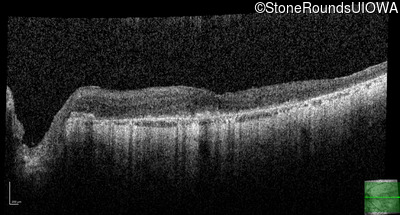

This 81 year old man began using a flashlight to read menus in his 40's. At age 75 his ophthalmologist noticed abnormal fundus findings and referred him to a retina specialist.

Diagnosis & molecular findings

| Disease | Gene | Allele 1 variant(s) | Allele 2 variant(s) | Inheritance mode |

|---|---|---|---|---|

| Late Onset Retinal Dystrophy | C1QTNF5 | Ser163Arg AGC>AGA | AD |

Disease:

Gene:

Allele 1:

Ser163Arg AGC>AGA

Allele 2:

Inheritance:

AD